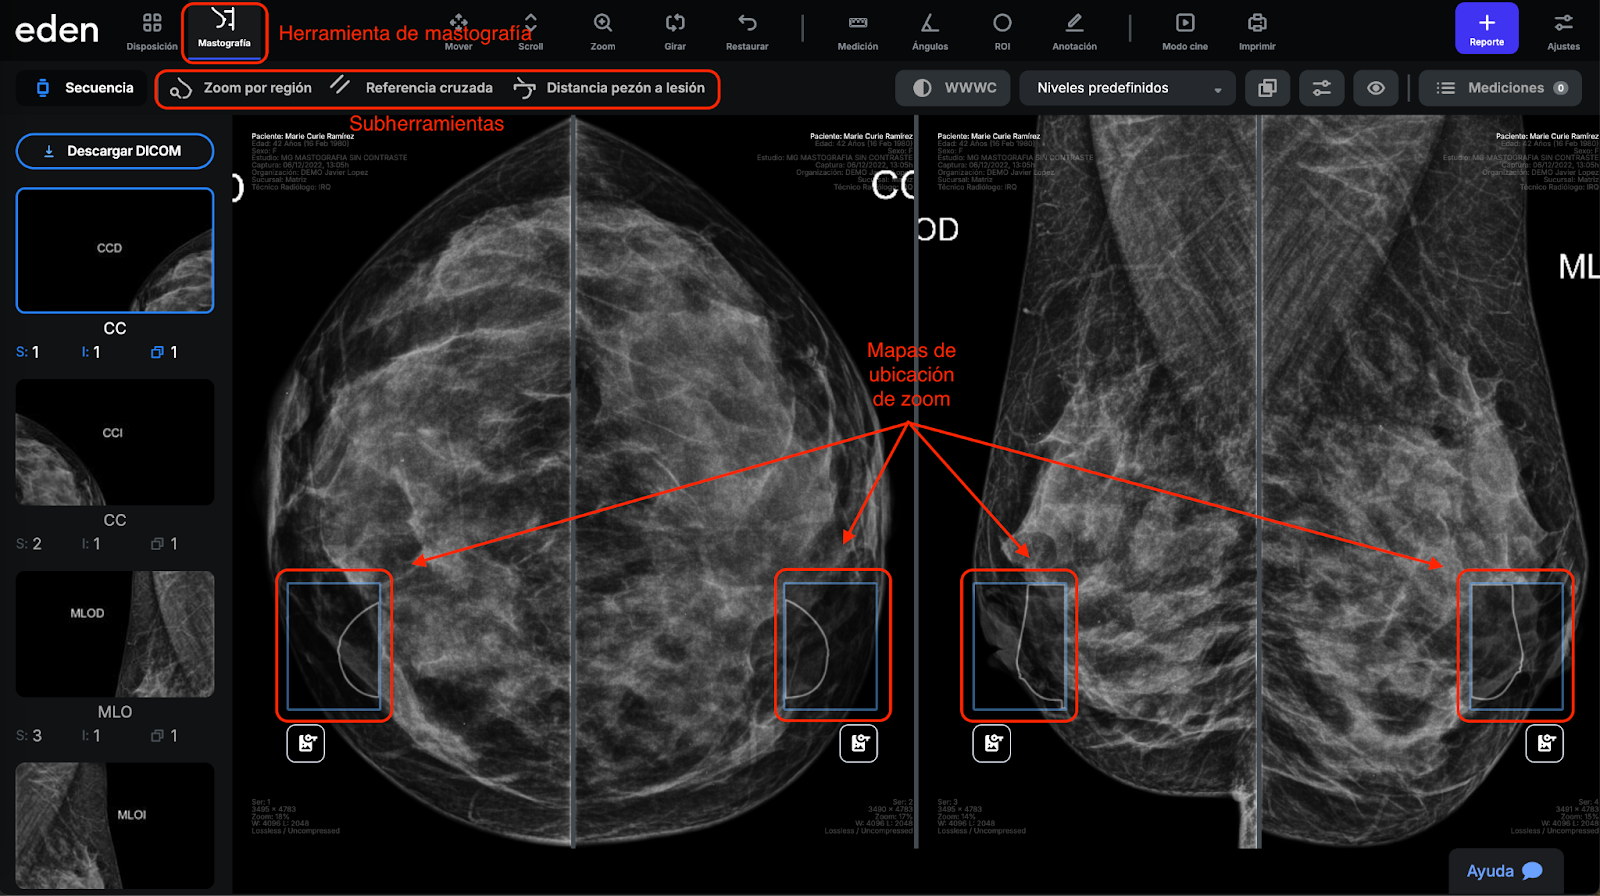

Mastografía: Esta herramienta solo aparece en estudios de mastografía. Nos muestra 3 sub herramientas enfocadas en este tipo de estudios:

Zoom por región. Esta herramienta hace un barrido en zoom sincronizado de la imagen. La posición del barrido se muestra en el mapa de ubicación en cada una de las vistas del estudio como muestra la siguiente imagen:

Referencia cruzada. Esta herramienta nos permite dar clic en un punto de una de las vistas (CC/ML/MLO) y en la otra vista del mismo lado nos mostrará un rango de ubicación con un intervalo de 2cm.

Distancia de pezón a lesión. Esta herramienta automáticamente resalta la región del pezón (en todas las vistas), de tal forma que cuando demos clic en un punto de interés, nos mostrará la distancia de dicho punto de interés al pezón.